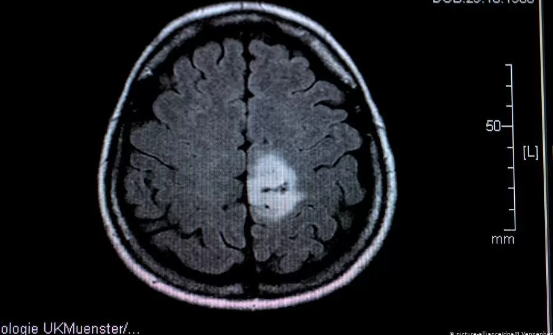

İngiltere merkezli Imperial College London'ın bir parçası olan Beyin Tümörü Araştırma Mükemmeliyet Merkezi tarafından yapılan araştırmalar, standart kan örnekleriyle hastalığın izlerini tespit edebildiklerini ortaya çıkardı.

Uzmanlar, bu yöntemin, çoğu beyin tümörünü teşhis etmek için kullanılan riskli cerrahi ihtiyacını azaltırken teşhis ve tedaviyi hızlandırabileceğini söylüyor.

Kullanılan "sıvı biyopsi"nin özellikle erişilemeyen beyin tümörleri olan hastalar için faydalı olacağını, böylece tedaviye mümkün olan en kısa sürede başlayabileceklerini söylediler.

Uluslararası Kanser Dergisi'nde yayınlanan bulguların önemli olduğunu söyleyen araştırmacılar, glioblastomalı hastaların yüzde 1'inden azının on yıldan fazla yaşadığını ve erken teşhisin önemli olduğunu kaydettiler.